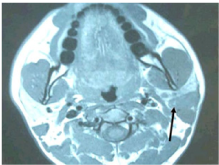

Ultrasonography (USG) of the neck revealed a lesion in left parotid with heterogenous echo texture with multiple enlarged lymph nodes at level II and II, largest measuring 1.3 x 1.7 x 2cm at level II on left. Initial FNAC showed pleomorphic adenoma and repeat USG guided Fine needle aspiration, which was repeated twice, showed suboptimal aspirate mixed with blood inadequate for opinion. MRI of the neck revealed multiple well defined lesions in left parotid gland, largest in the superficial lobe and tail of parotid and extending into the deep lobe measuring 32.6 x 20.4 x 22mm and two separate lesions in the deep lobe of the parotid largest being 9.4 x 7.3mm. Also, there were multiple subcentimeter lymp nodes noted at level IIb, III and IV bilaterally. Features suggestive of ‘Multicentric Warthin’s tumour left parotid gland’.

A total parotidectomy with preauricular skin incision was planned. However, intra-operatively involvement of surrounding muscles, periparotid lymph nodes and level II b / III lymph nodes was noted. Facial nerve and its terminal branches were preserved with careful dissection, however there was adherence of inferior division of facial nerve to the tumour mass which was cleared carefully under microscopic control. The retromandibular vein was ligated and a globular mass seen arising from the deep lobe of the parotid. The tumour was removed in to along with other smaller mass from the deep lobe. Total parotidectomy was performed along with excision of unhealthy overlying skin, part of upper and anterior border of Sternocleidomastoid muscle and a part of posterior belly of Digastric muscle. Level II b and III lymph node clearance was done. A suction drain was put for 48hours. Post operative recovery was uneventful with minimal deviation of angle of the mouth which recovered fully after two weeks. Histopathology of the mass revealed diffuse large B cell NHL showing sheets and strands of atypical lymphoid cells with involvement of superficial, deep lobe of parotid, Sternocleidomastoid muscle and Digastric muscle. Skin and level IIb and III lymph nodes also revealed similar population of atypical cells with perinodal extension. The tumour cells were positive strongly for CD20, LCA and CD79a on Immunohistochemistry (IHC). However, the cells were negative for CD5, CD3, EMA, CK and TdT on IHC. The Ki-67 labelling index was 100% (Figures 3-8).